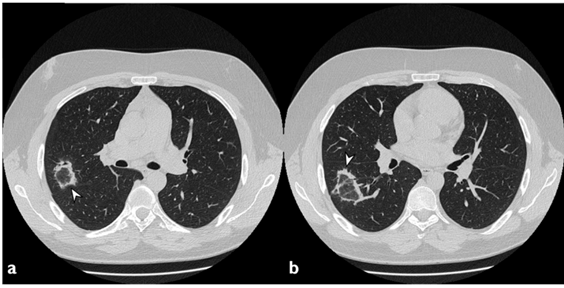

2. 影像学表现

①肺实变磨玻璃密度影;②小叶周围阴影;③环礁征;④结节或肿块;⑤小叶间隔增厚;⑥束状或条带阴影;⑦进行性纤维化。

分布于周围的多灶性和非对称实变

图片

3. 影像学特点

(1)典型影像:斑片状肺泡浸润影(典型COP)。

(2)不常见影像:孤立性阴影(局灶性COP);浸润性阴影(浸润性COP)。

4. 影像学的鉴别诊断

(1)多发型片状肺泡渗出影:需与嗜酸性粒细胞肺炎(慢性)、肺泡细泡癌-肺炎型、原发性肺淋巴瘤、吸入性肺炎及其他疾病[如感染性肺炎、结核或非结核性分支杆菌感染、肉芽肿并血管炎(韦格氏肉芽肿)、弥漫性肺泡出血、多发性肺梗死进行鉴别。

(2)孤立性灶性结节或肿块:需与肺癌、圆形肺炎、炎性假瘤及其他结节或肿块疾病进行鉴别。

(3)进行性/致纤维化型COP:与特发性间质性肺炎(尤其是非特异性间质性肺炎和特发性肺纤维化急性加重)以及其他感染、肿瘤性病变进行鉴别。